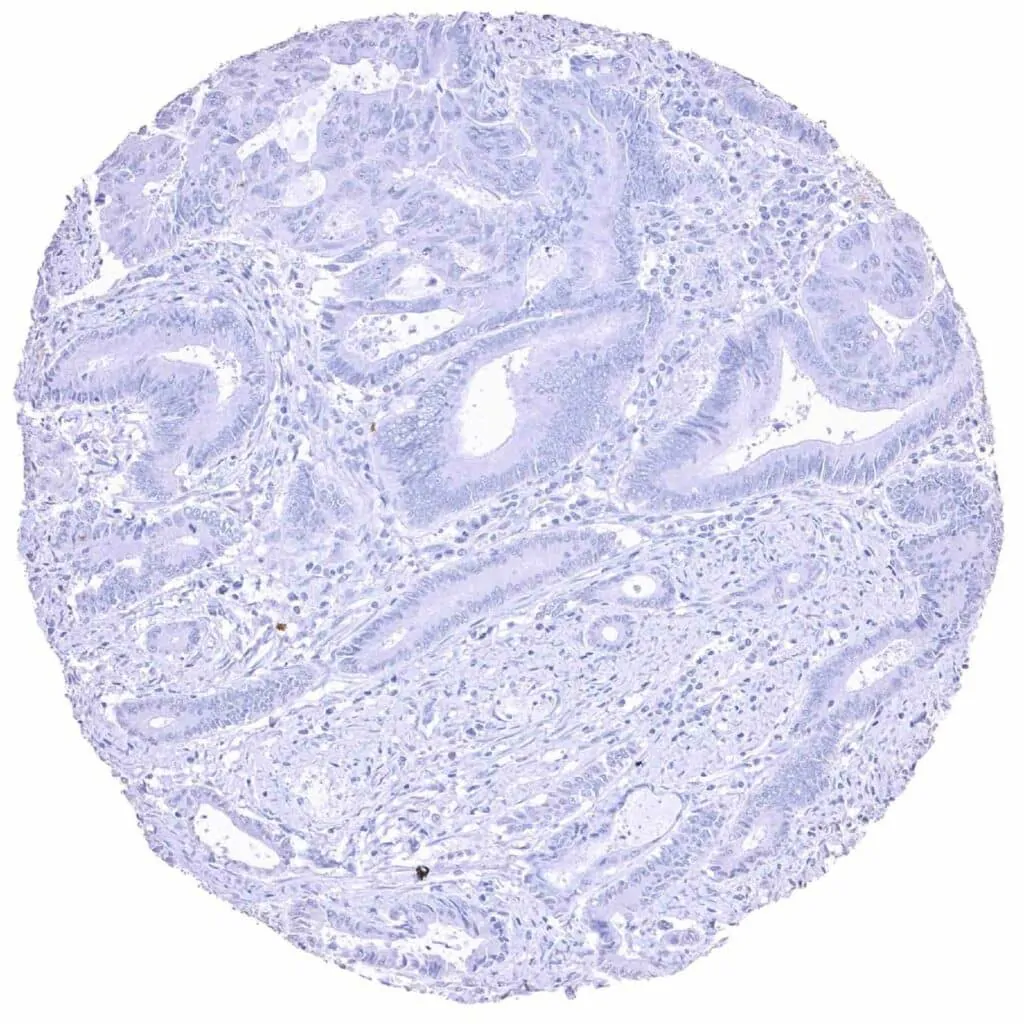

Colon – MYH7 negative colorectal adenocarcinoma